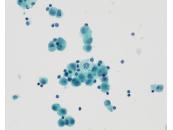

第36回日本臨床細胞学会九州連合会学会(大分)スライドカンファレンス症例4

種別:体腔液

出題:宮崎県立宮崎病院 病理診断科 丸塚 浩助

| 年齢 | 50代後半 | 性別 | 女性 |

|---|---|---|---|

| 採取部位 | 腹水 | 採取方法 | 穿刺 |

| 検体処理法 | 塗抹及びLBC |

臨床所見

<既往歴>

特記なし

<現病歴>

2ヶ月前頃より腹部膨満・下腿浮腫を自覚し、当院産婦人科に紹介受診。MRIにて著明な腹水と骨盤腔内を占める腫瘤が認められ、癌性腹水を伴う卵巣癌との臨床診断で腹水穿刺細胞診が行われた。

化学療法後開腹手術を行ったが、びまん性腹膜播種を認め、腫瘍切除のみ行われた。腫瘍はS状結腸腸間膜に存在し、卵巣・子宮は正常外観であった。

| 正解 | 5.炎症性筋線維芽細胞肉腫 |

▼選択肢及び投票結果

| 1.卵巣漿液性腺癌 | 5件 | (7.8%) | |

| 2.腹膜中皮腫 | 3件 | (4.7%) | |

| 3.消化管間質腫瘍 | 1件 | (1.6%) | |

| 4.未分化大細胞リンパ腫 | 42件 | (65.6%) | |

| 5.炎症性筋線維芽細胞肉腫 | 13件 | (20.3%) | |

| 投票総数 | 64件 | (100%) |